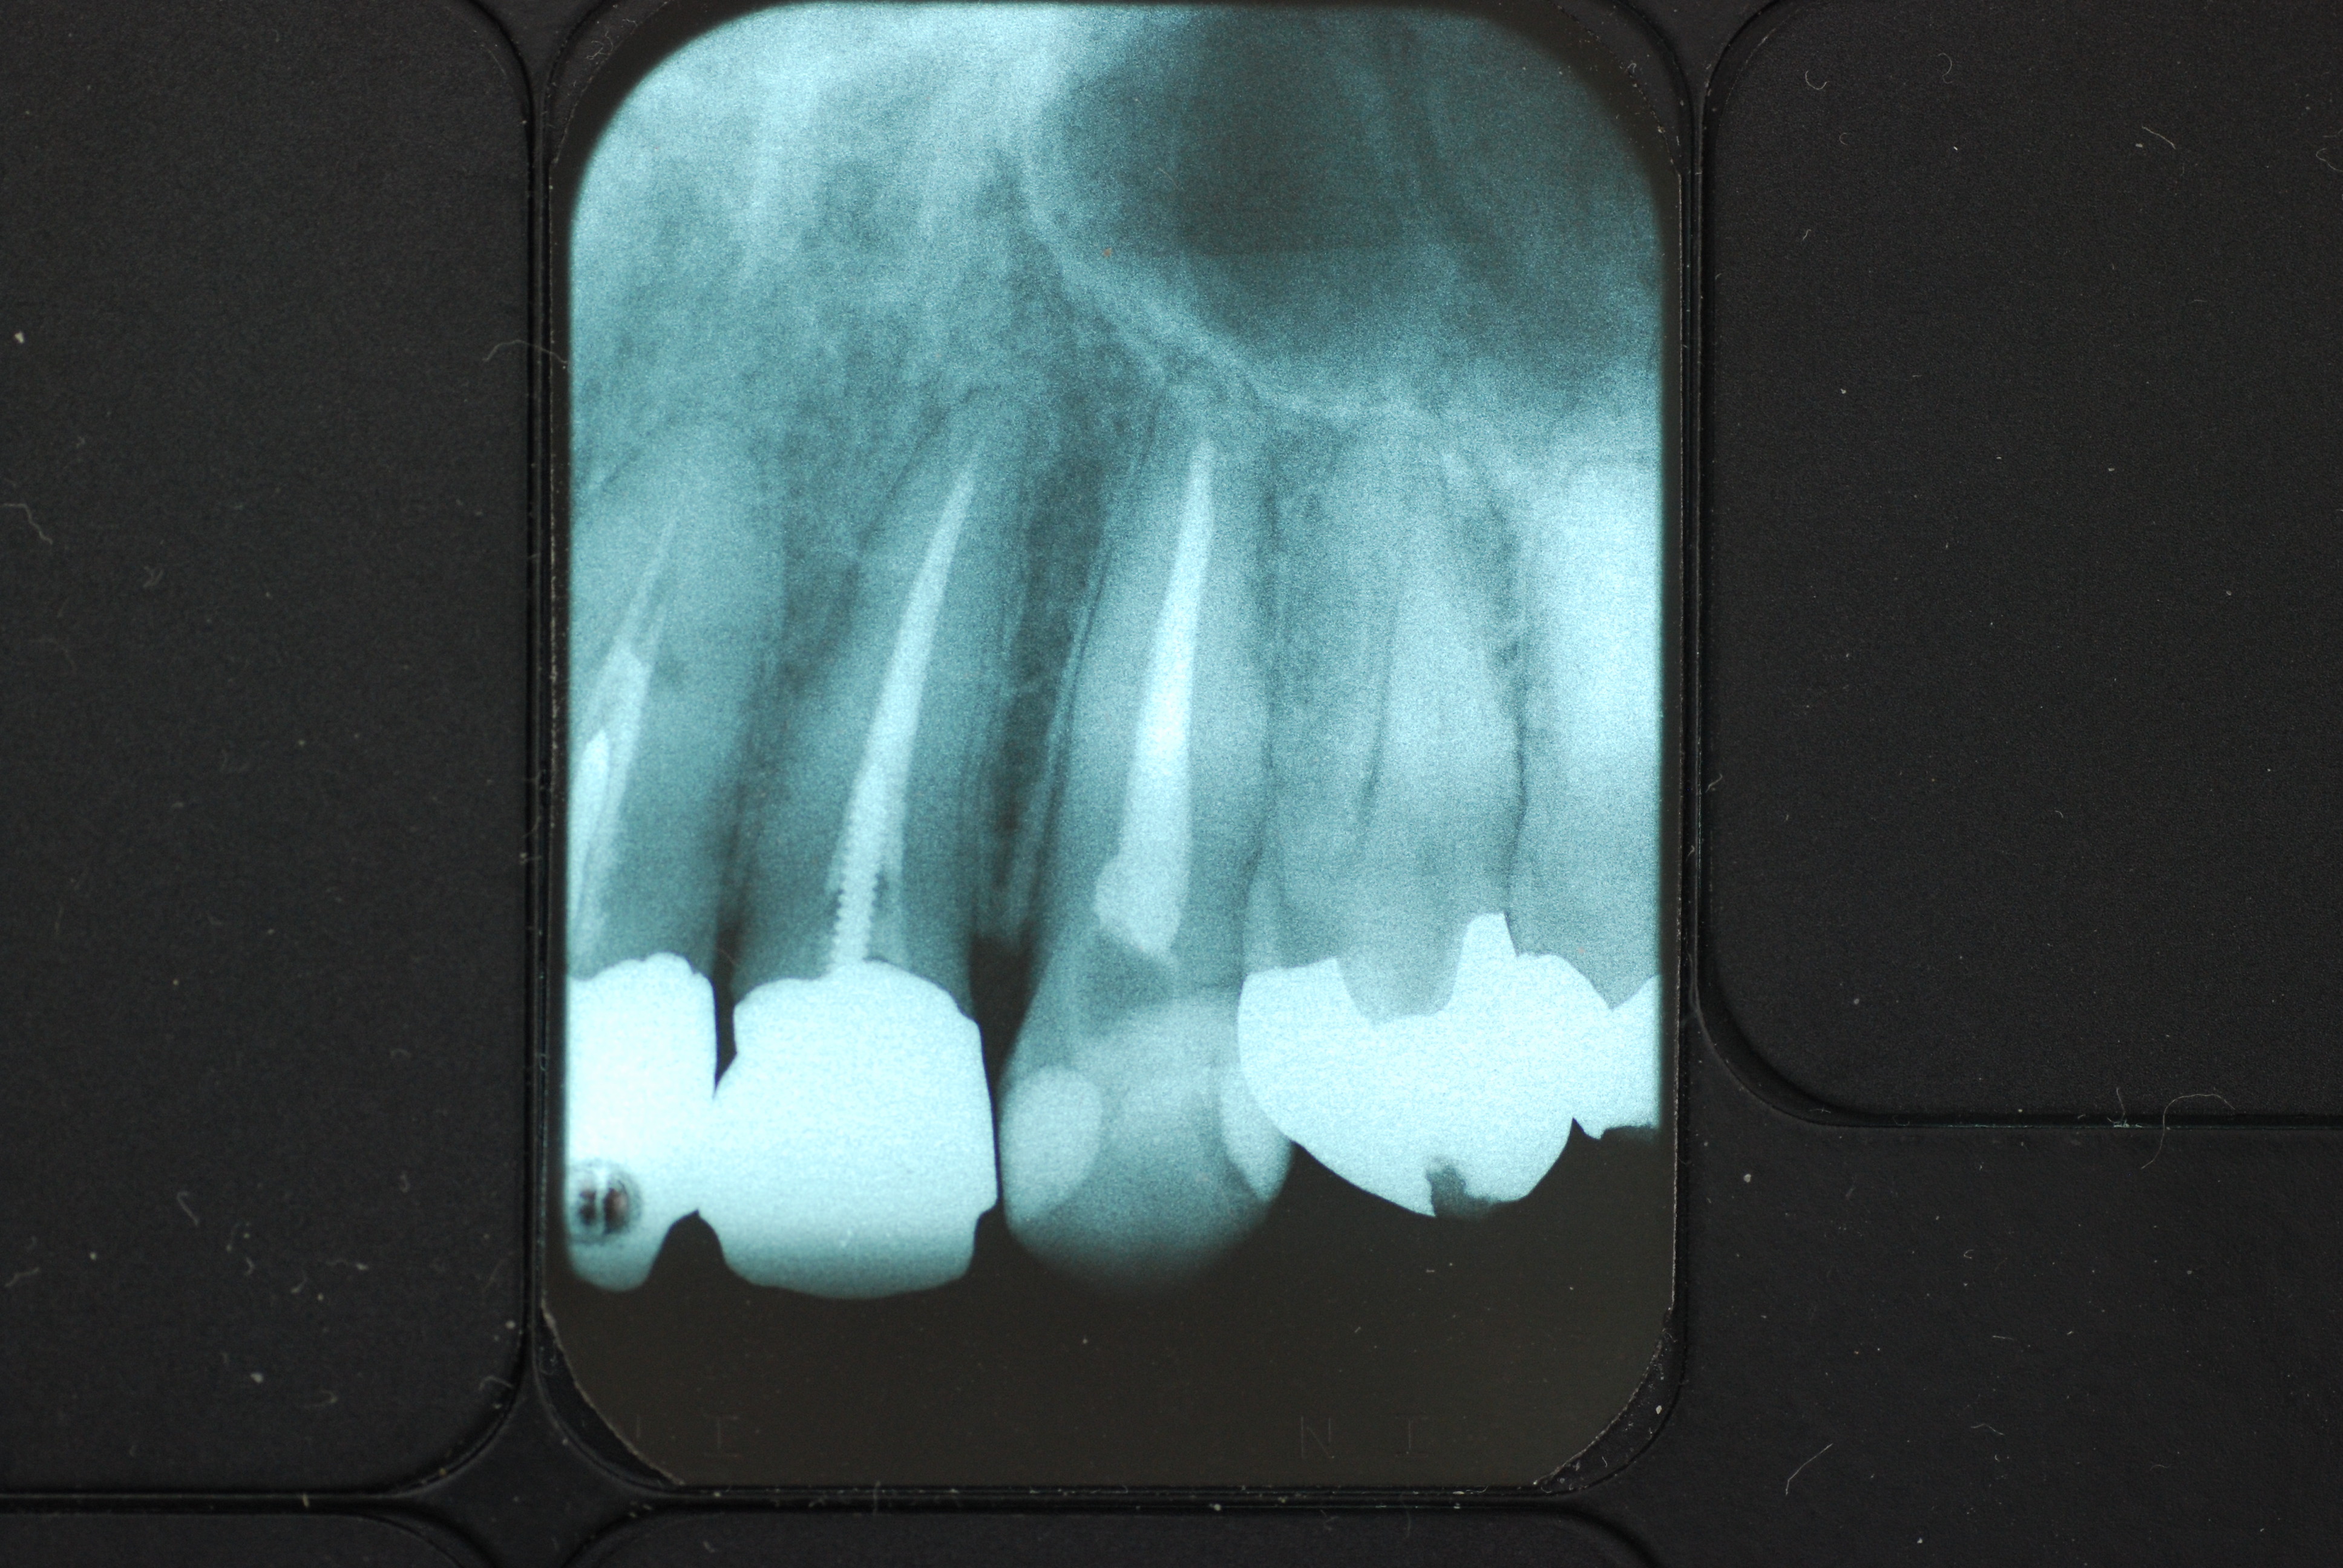

下の写真の方は虫歯と歯の間の歯周病が酷かったのです。

虫歯の治療も完全にできませんし、歯の位置が悪く又重なっている為に歯周病が治らずに説得に数カ月を有した後に矯正することになりました。

写真左の歯のうち過剰歯と糸きり歯の隣を抜きました。